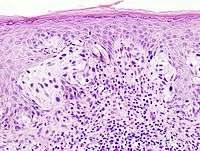

A biopsy is a small piece of tissue removed primarily for the purposes of surgical pathology analysis, most often in order to render a definitive diagnosis. Types of biopsies include core biopsies, which are obtained through the use of large-bore needles, sometimes under the guidance of radiological techniques such as ultrasound, CT scan, or magnetic resonance imaging. Core biopsies, which preserve tissue architecture, should not be confused with fine needle aspiration specimens, which are analyzed using cytopathology techniques. Incisional biopsies are obtained through diagnostic surgical procedures that remove part of a suspicious lesion, whereas excisional biopsies remove the entire lesion, and are similar to therapeutic surgical resections. Excisional biopsies of skin lesions and gastrointestinal polyps are very common. The pathologist's interpretation of a biopsy is critical to establishing the diagnosis of a benign or malignant tumor, and can differentiate between different types and grades of cancer, as well as determining the activity of specific molecular pathways in the tumor. This information is important for estimating the patient's prognosis and for choosing the best treatment to administer. Biopsies are also used to diagnose diseases other than cancer, including inflammatory, infectious, or idiopathic diseases of the skin and gastrointestinal tract, to name only a few.

- Dermatopathology (A board-certifiable subspecialty in the U.S.)